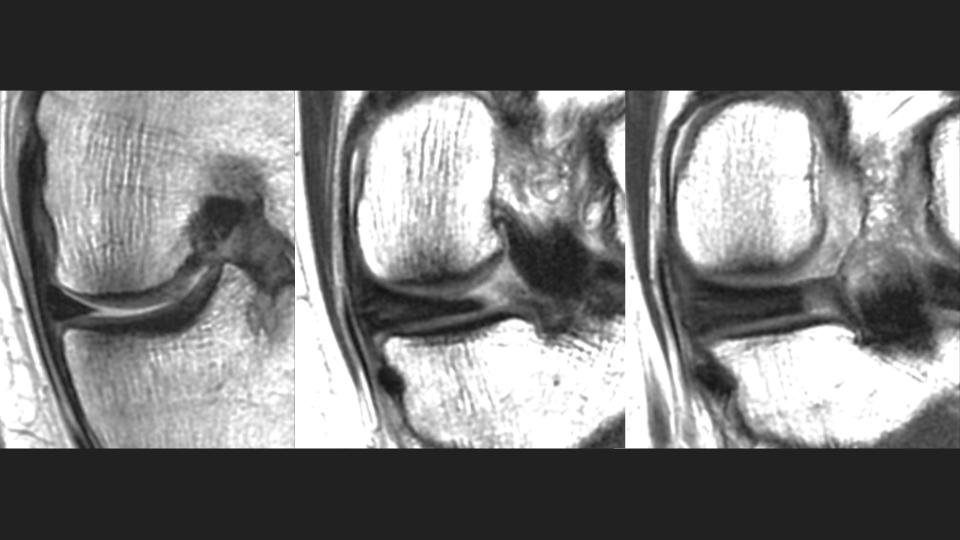

49M runner with pain since twisting injury during marathon 1 year ago

There is a radial tear / avulsion of the posterior horn medial meniscal root (red arrow), which is likely related to the running injury 1 year ago. There is stress related marrow edema, but it is not localized deep to the root anchor. There is 3mm (borderline) extrusion of the medial meniscal body (white arrow), but there is surprising preservation of the medial compartment articular cartilage. Meniscal root tear is known to predispose to medial compartment cartilage loss, which is often rapid. Hes obviously symptomatic and has stress related marrow edema, but why hasnt he developed medial compartment OA?

posterior horn of medial meniscus ( RID2776 )